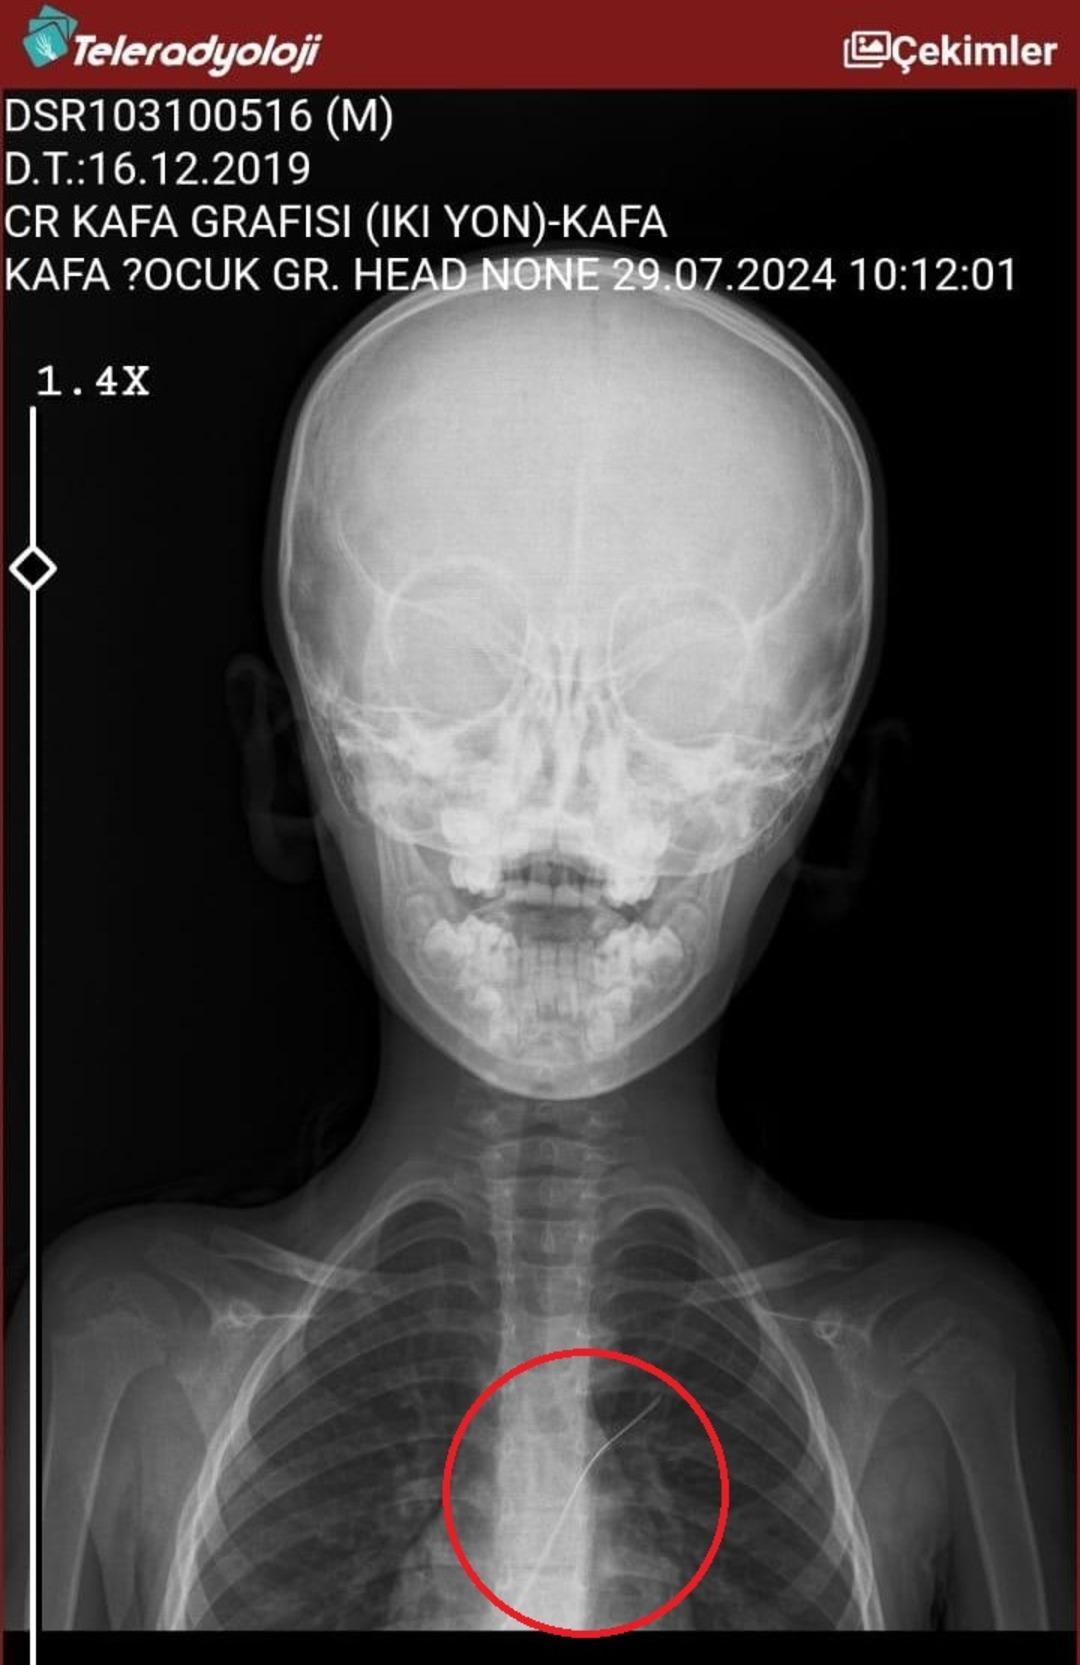

Seamore (37) ve Şaç'ta yaşayan Mehmet Ötün (40), Mayıs ayında bir parça salatalık yuttuktan sonra öksürük ve kusma şikayetleri gözlendiğinde Sernak Eyalet Hastanesine getirildi. Burada, ARAM gövdesinde yarıçap X ve manyetik rezonans görüntüleme unutuldu. Diyarbakir Gazi Yeşargil'in eğitim ve araştırma hastanesi jinekolojiye ve ARAM'lar için ek binaya yönlendirildi, 18 santimetrede 5.5 saatlik riskli cerrahi kaldırıldı. Postoperatif araştırmalarda, kateter kalp kapakına ve karaciğere zarar vermeye kararlıydı.

Otün, oğlunun piknikte bir parça salatalık yuttuktan sonra atmaya ve kusmaya başladığını söyledi: “Oğlum 3 yıl önce Steven Johnson sendromu hastalığında yakalandı. Milyonda görülen bir antibiyotik hastalığı.